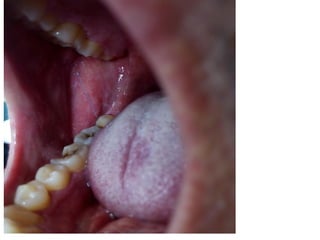

• 2 vết loét miệng ở niêm mạc nứu răng cửa

dưới, d # 1-2cmm, đáy sạch, đau khi ăn.

• Hạch cổ